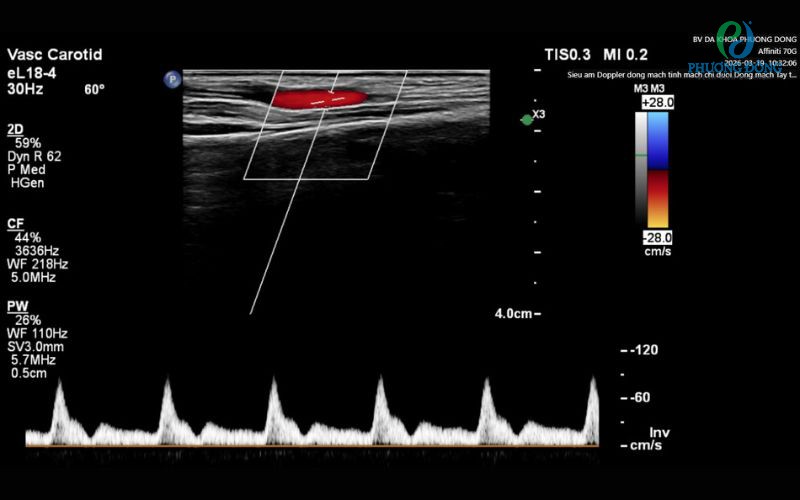

Siêu âm Doppler là kỹ thuật siêu âm màu kết hợp Doppler sử dụng sóng âm cao tần (2–10 MHz) để:

• Đo chính xác vận tốc dòng máu (peak systolic velocity – PSV, end-diastolic velocity – EDV), chỉ số kháng lực (RI), chỉ số xung (PI).

Nói dễ hiểu: giống như “chụp video HD + đo tốc độ xe” của dòng máu trong mạch bạn. Máy sẽ hiển thị màu đỏ/xanh (hướng chảy), đồ thị sóng (spectral Doppler) và hình ảnh 2D siêu rõ nét. Không dùng tia X, không chất tương phản, an toàn tuyệt đối cho mọi đối tượng kể cả trẻ em và bà bầu.

• Phân tích: Máy hiện ngay hình ảnh màu, đồ thị sóng Doppler, chỉ số chính xác. Bác sĩ chuyên khoa Chẩn đoán hình ảnh giải thích ngay kết quả, in màu hoặc lưu file điện tử.